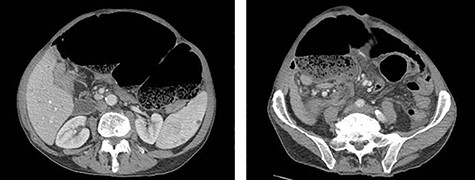

Exploratory laparotomy revealed a massively dilated cecum and right colon with complete 360-degree clockwise rotation along the ileocolic pedicle. The right colon and cecum were eviscerated from the abdomen (Fig. 3). The colon was viable, but extremely dilated and thin walled. The proximal region of the volvulus was identified, and the distal ileum was divided. A decompressed region of transverse colon was identified as the distal region of the volvulus. There were extensive adhesions involving the afferent biliopancreatic limb and the gastrojejunal anastomosis to the transverse mesocolon. Once mobilized, the transverse colon was divided to the right of the middle colic vessels. The specimen was detorsed immediately prior to division of the ileocolic pedicle, and ileocolic anastomosis was performed. Four small (<2 cm) uninvolved peritoneal implants were identified, removed and sent for permanent pathology.